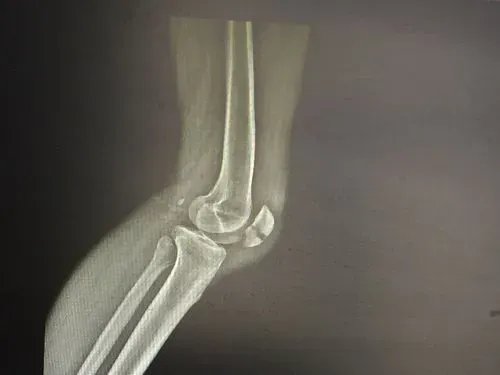

髌骨骨折患者髌骨骨折后会自觉膝盖疼痛、乏力,不能伸直膝关节站立。X线平片可见横行骨折线,关节面不连续,可见撕裂的小骨折片,多移位或呈粉碎性。